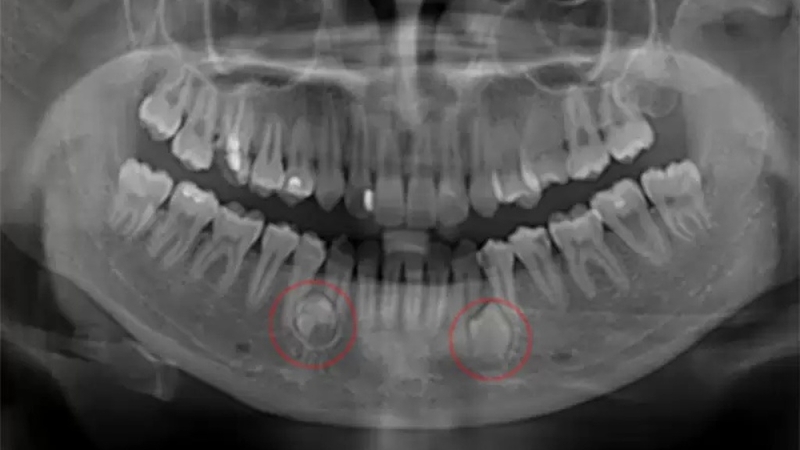

- Sau 3 tháng: Chụp X-quang kiểm tra lần đầu

- Sau 6 tháng: Đánh giá quá trình tái tạo xương

- Sau 1 năm: Xác nhận hết nang hoàn toàn

- Định kỳ mỗi năm trong 3-5 năm tiếp theo (với nang có nguy cơ tái phát cao)

Đặc biệt lưu ý: Nhiều trường hợp nang tái phát không có triệu chứng rõ ràng trong giai đoạn đầu. Đây là lý do việc tái khám đúng lịch và chụp X-quang định kỳ vô cùng quan trọng – giúp phát hiện sớm trước khi nang kịp phát triển lớn.